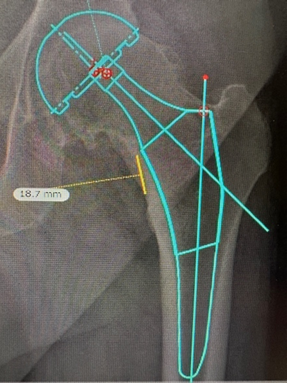

D: Molti di questi interventi vengono eseguiti anche grazie all’uso della robotica?

R: Il robot viene generalmente utilizzato per posizionare meglio la componente acetabolare. Uno dei problemi dell'intervento di sostituzione dell'anca è rappresentato dalla lussazione, o fuoriuscita della testa del femore dall’acetabolo. Questa complicazione può essere dovuta ad una non ottimale posizione della protesi alveolare. Il robot ne consente un più preciso posizionamento.